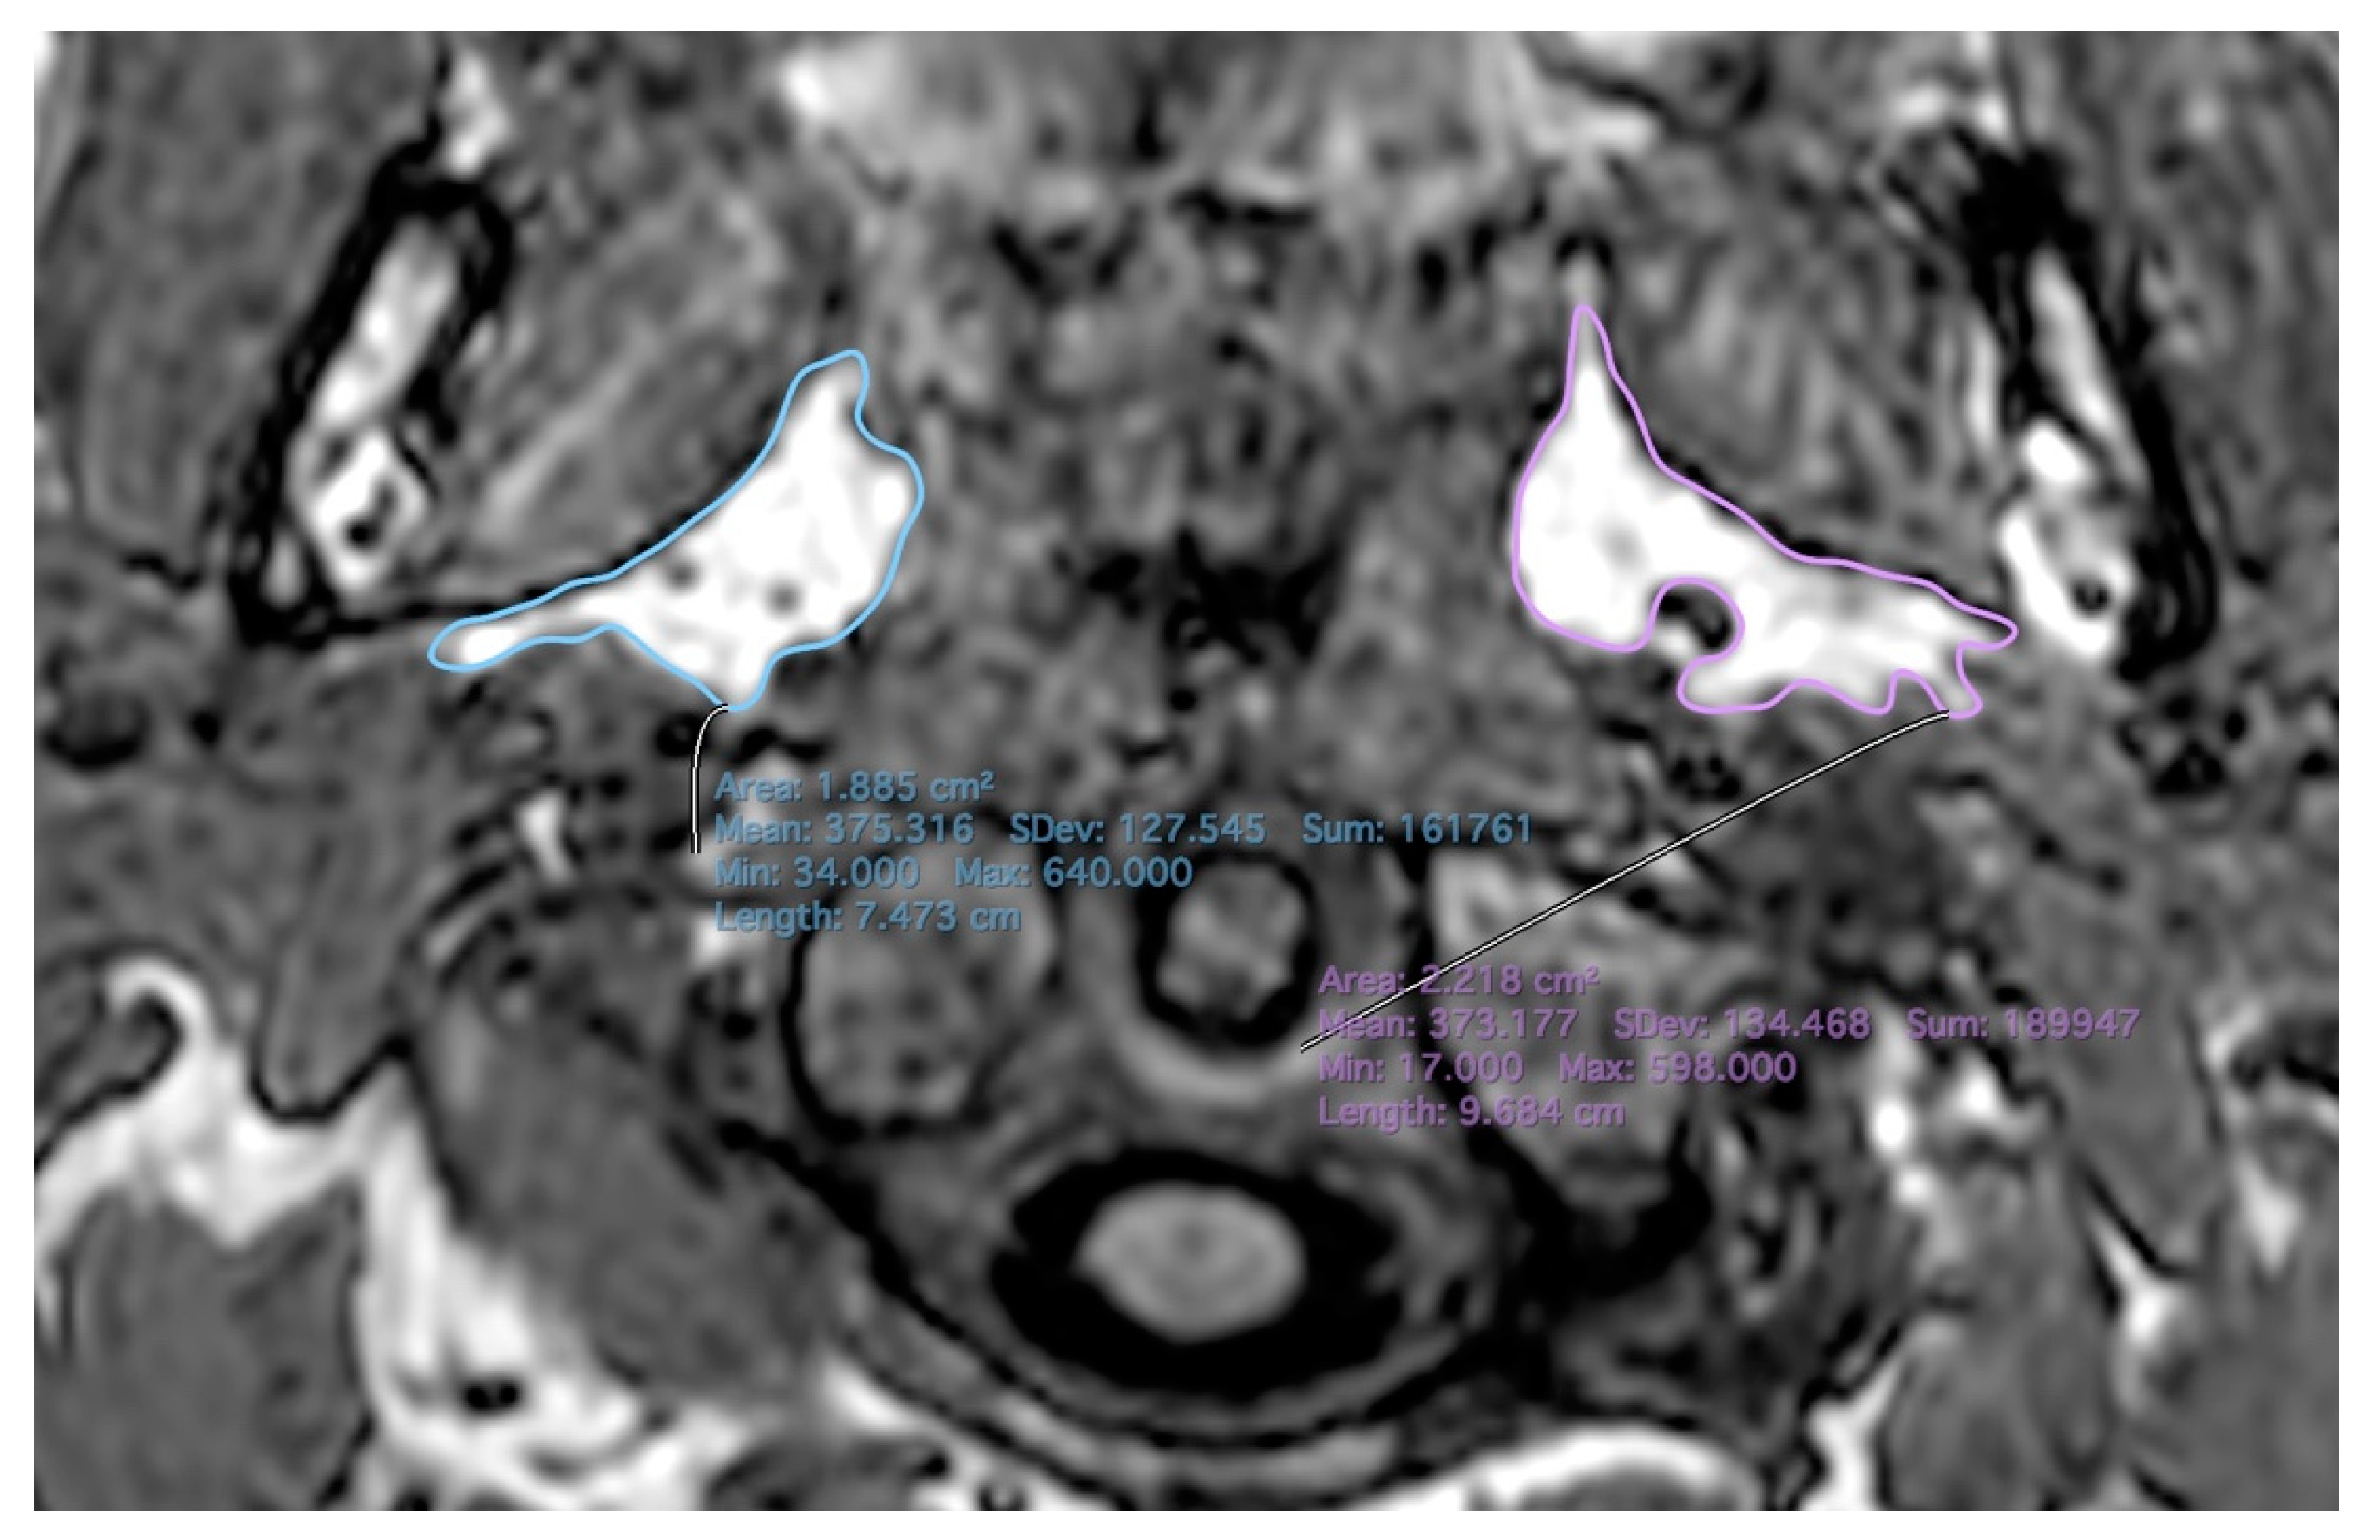

2.2. MR Imaging